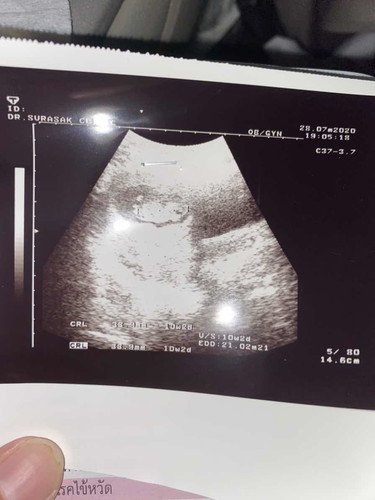

รูปอัลตร้าซาวจ้าตอน10วีค2วัน เห็นแขนเห็นขาน้องดุ้กดิ้กอยู่ในท้องแล้ว แต่แม่ยังไม่รู้สึกเลยจ้า😅

* น้องตัวประมาณ3-4เซ็นเองงับแม่ เดี๋ยวอายุครรภ์เยอะขึ้นก็รู้สึกคร้าบ ถ้าท้องบางจะรู้สึกเร็วค่ะ